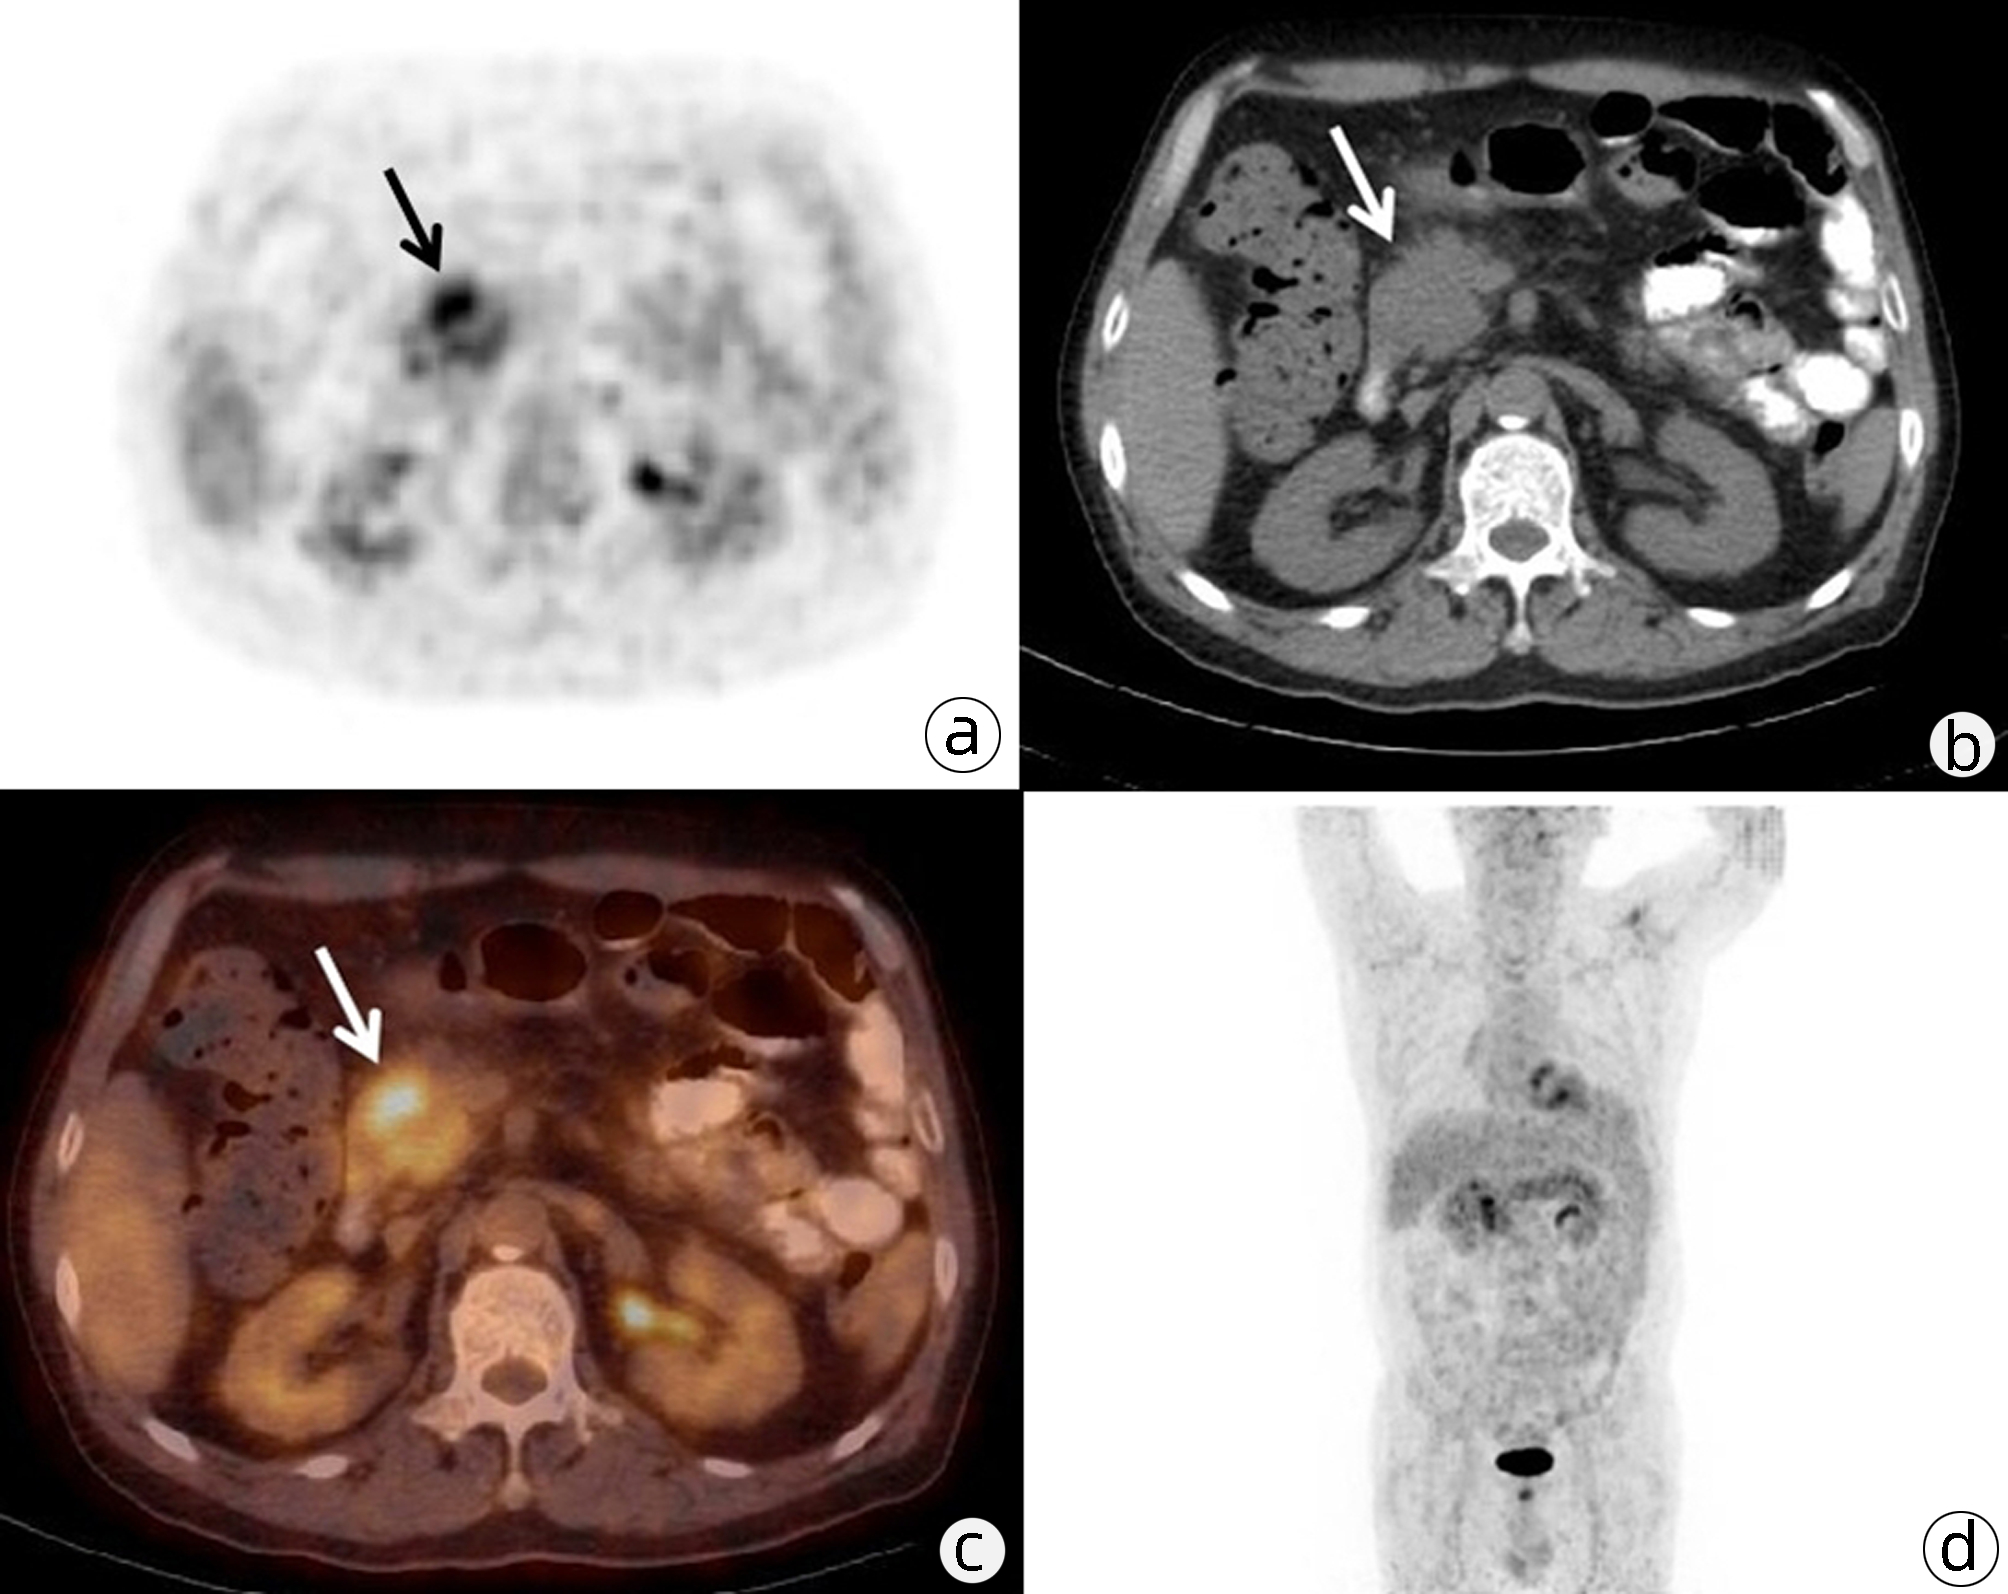

Value of 18F-FDG PET/CT, contrast-enhanced ultrasound, and their combined use in differential diagnosis of benign and malignant pancreatic lesions: A comparative study

Lichun ZHENG, Xiaoming ZHANG, Tianying YU, Jie LI, Xiaoqian DENG, Xiangliu OUYANG

2022, 38(12): 2774-2779. DOI: 10.3969/j.issn.1001-5256.2022.12.017

Abstract(2330) HTML (1630) PDF (3391KB)(64)

Abstract:

Objective  To assess the value of 18F-FDG PET/CT, contrast-enhanced ultrasound, and their combination in the differential diagnosis of benign and malignant pancreatic lesions.  Methods  A retrospective analysis was performed on patients with pancreatic lesions who underwent18F-FDG PET/CT and contrast-enhanced ultrasound who were admitted to Tangshan Gongren Hospital from January 2015 to December 2020. The imaging results were confirmed by pathology examination to evaluate diagnostic sensitivity, specificity, accuracy, positive and negative predictive value. The t-test was used for comparison of continuous data between two groups, and the chi-square test was used for comparison of categorical data between groups.  Results  There were 83 malignant lesions and 25 benign lesions in 108 patients. The sensitivity, specificity, accuracy, positive and negative predictive value were 86.75%, 80.00%, 85.19%, 93.51% and 64.52% for 18F-FDG PET/CT; and 69.88%, 76.00%, 71.30%, 90.63% and 43.18% for contrast-enhanced ultrasound, respectively. The two methods differed significantly in sensitivity and accuracy (all P < 0.05), but not in specificity, negative and positive predictive value (all P > 0.05). When combined with the contrast-enhanced ultrasound, 18F-FDG PET/CT had an increased sensitivity, specificity, accuracy, positive and negative predictive value of 90.36%, 84.00%, 88.89%, 94.94% and 72.41%, respectively, though this was not statistically significant due to the increased signal of blood supply in the lesions.  Conclusion  18F-FDG PET/CT has a better performance than contrast-enhanced ultrasound in the differential diagnosis of benign and malignant pancreatic lesions, and their combination can improve the diagnostic value.